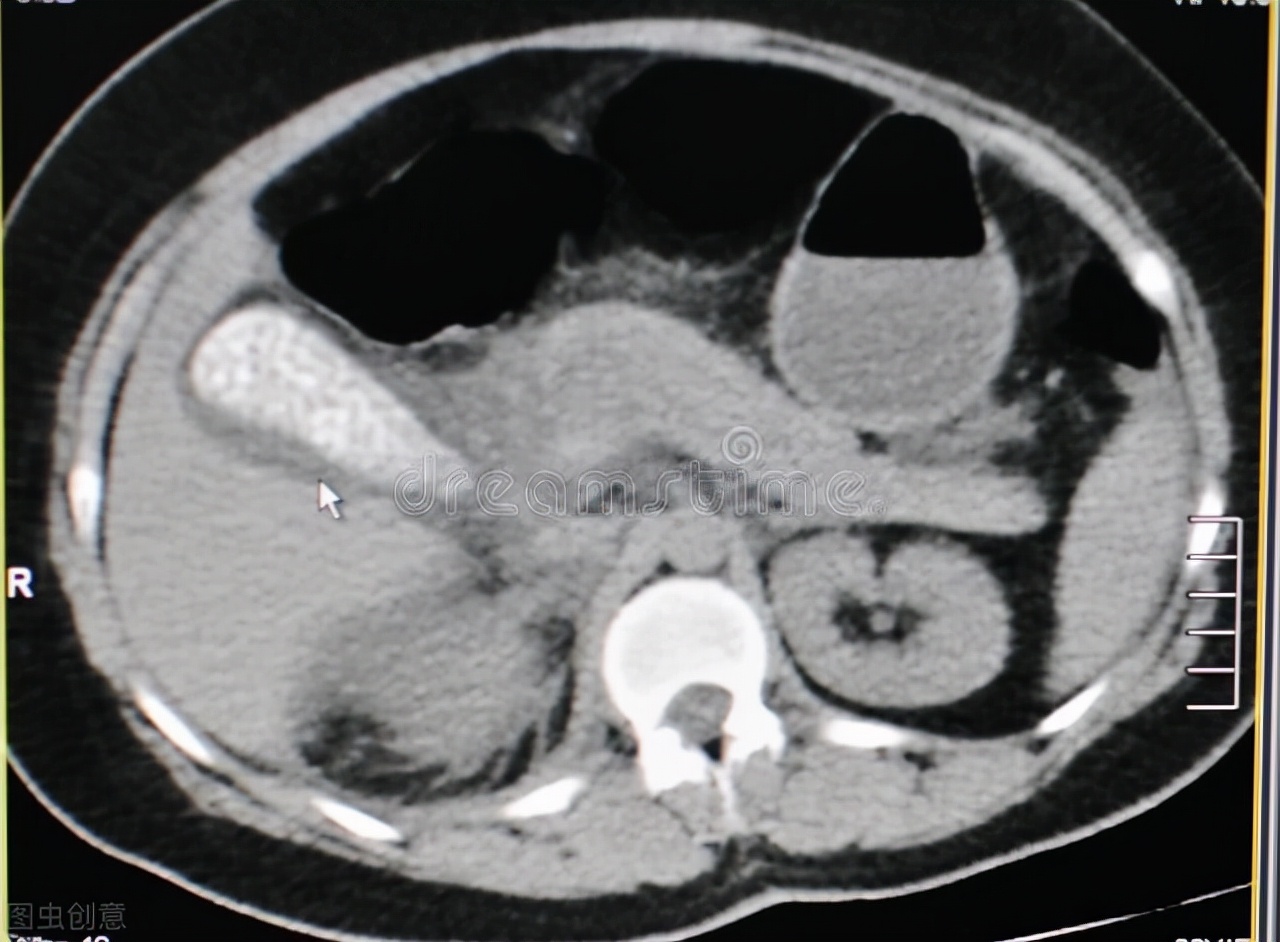

胃底静脉曲张?为什么会这样,难道是肝脏出了问题导致的门静脉高压?医生们又安排陶姐进行了肝脏的B超和CT检查,这一次终于发现了问题。

胰腺占位性病变

在B超下可以清楚地看到肝脏内有散在多个圆形或不规则性的分叶状实性肿物,四周毛糙,进行深压测量发现肿块无明显变形,初步考虑肝转移占位性病变。随即,肝脏CT也发现了明显的转移灶,而更加证实了,胰腺已经发生了广泛的占位性病变。

再者胰腺处于中上腹的深部,外面有大网膜覆盖,胰头隐藏在十二指肠的C型弯内,因此腹部B超一般情况下都比较难以观察到胰腺。大多数时候,胰腺病变的确诊都是依靠CT,甚至是增强CT。由于CT价格普遍贵于B超,因此可能很多人就拒绝了这个检查。